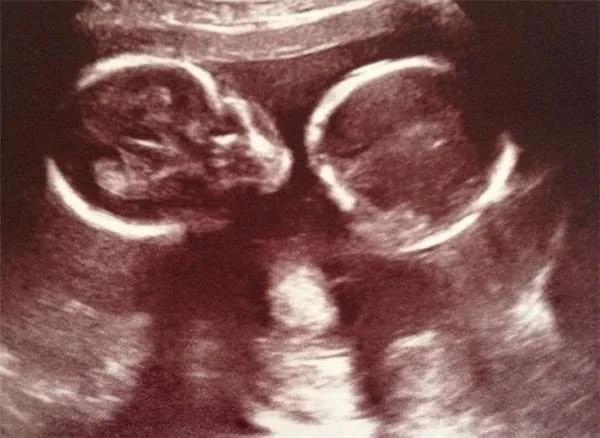

莎拉(Sarah Maund)得知自己雙胞胎的時,她和丈夫丹(Dan)可是又驚又喜,不過當懷孕22周到醫院產檢時,醫生的話卻讓他們陷入了憂慮之中…當時醫生用高科技儀器清晰拍到胎兒的許多畫面,子宮內的雙胞胎樣貌清楚呈現。

但醫生看完這些照片卻臉色大變,原來看似溫馨的照片,其實是雙胞胎兄弟的求救訊號,此時的亨利(Henry)和塞巴斯蒂安(Sebastian)面臨著危險,正在努力的活下去。

這對雙胞胎罹患了雙胎輸血綜合征(TTTS),雙胎輸血綜合征的發生機率約10-15%,是一種發生在雙胞胎間,血液不成比例的併發症。

亨利從胎盤獲得的血液較少,產生貧血的癥狀,而塞巴斯蒂安則是獲得過多血液,造成心臟負擔。